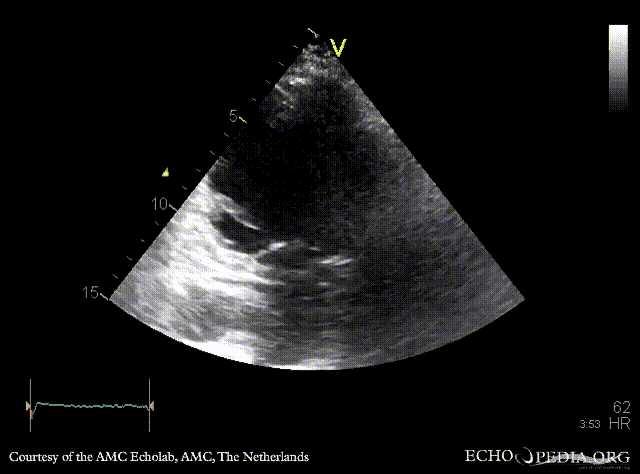

E00707.gif E00708.gif

A4CH: dilated left ventricle, poor function, akinesia of inferoseptal wall A2CH: dilated left ventricle, poor function, akinesia of inferior wall